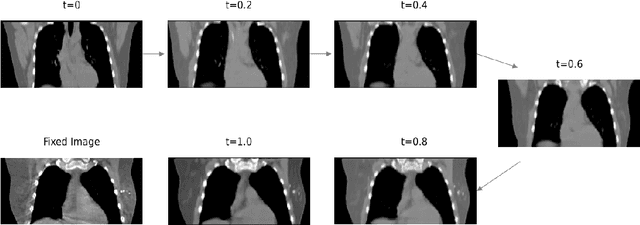

Abstract:We propose a flow-based registration framework of medical images based on implicit neural representation. By integrating implicit neural representation and Large Deformable Diffeomorphic Metric Mapping (LDDMM), we employ a Multilayer Perceptron (MLP) as a velocity generator while optimizing velocity and image similarity. Moreover, we adopt a coarse-to-fine approach to address the challenge of deformable-based registration methods dropping into local optimal solutions, thus aiding the management of significant deformations in medical image registration. Our algorithm has been validated on a paired CT-CBCT dataset of 50 patients,taking the dice coefficient of transferred annotations as an evaluation metric. Compared to existing methods, our approach achieves the state-of-the-art performance.